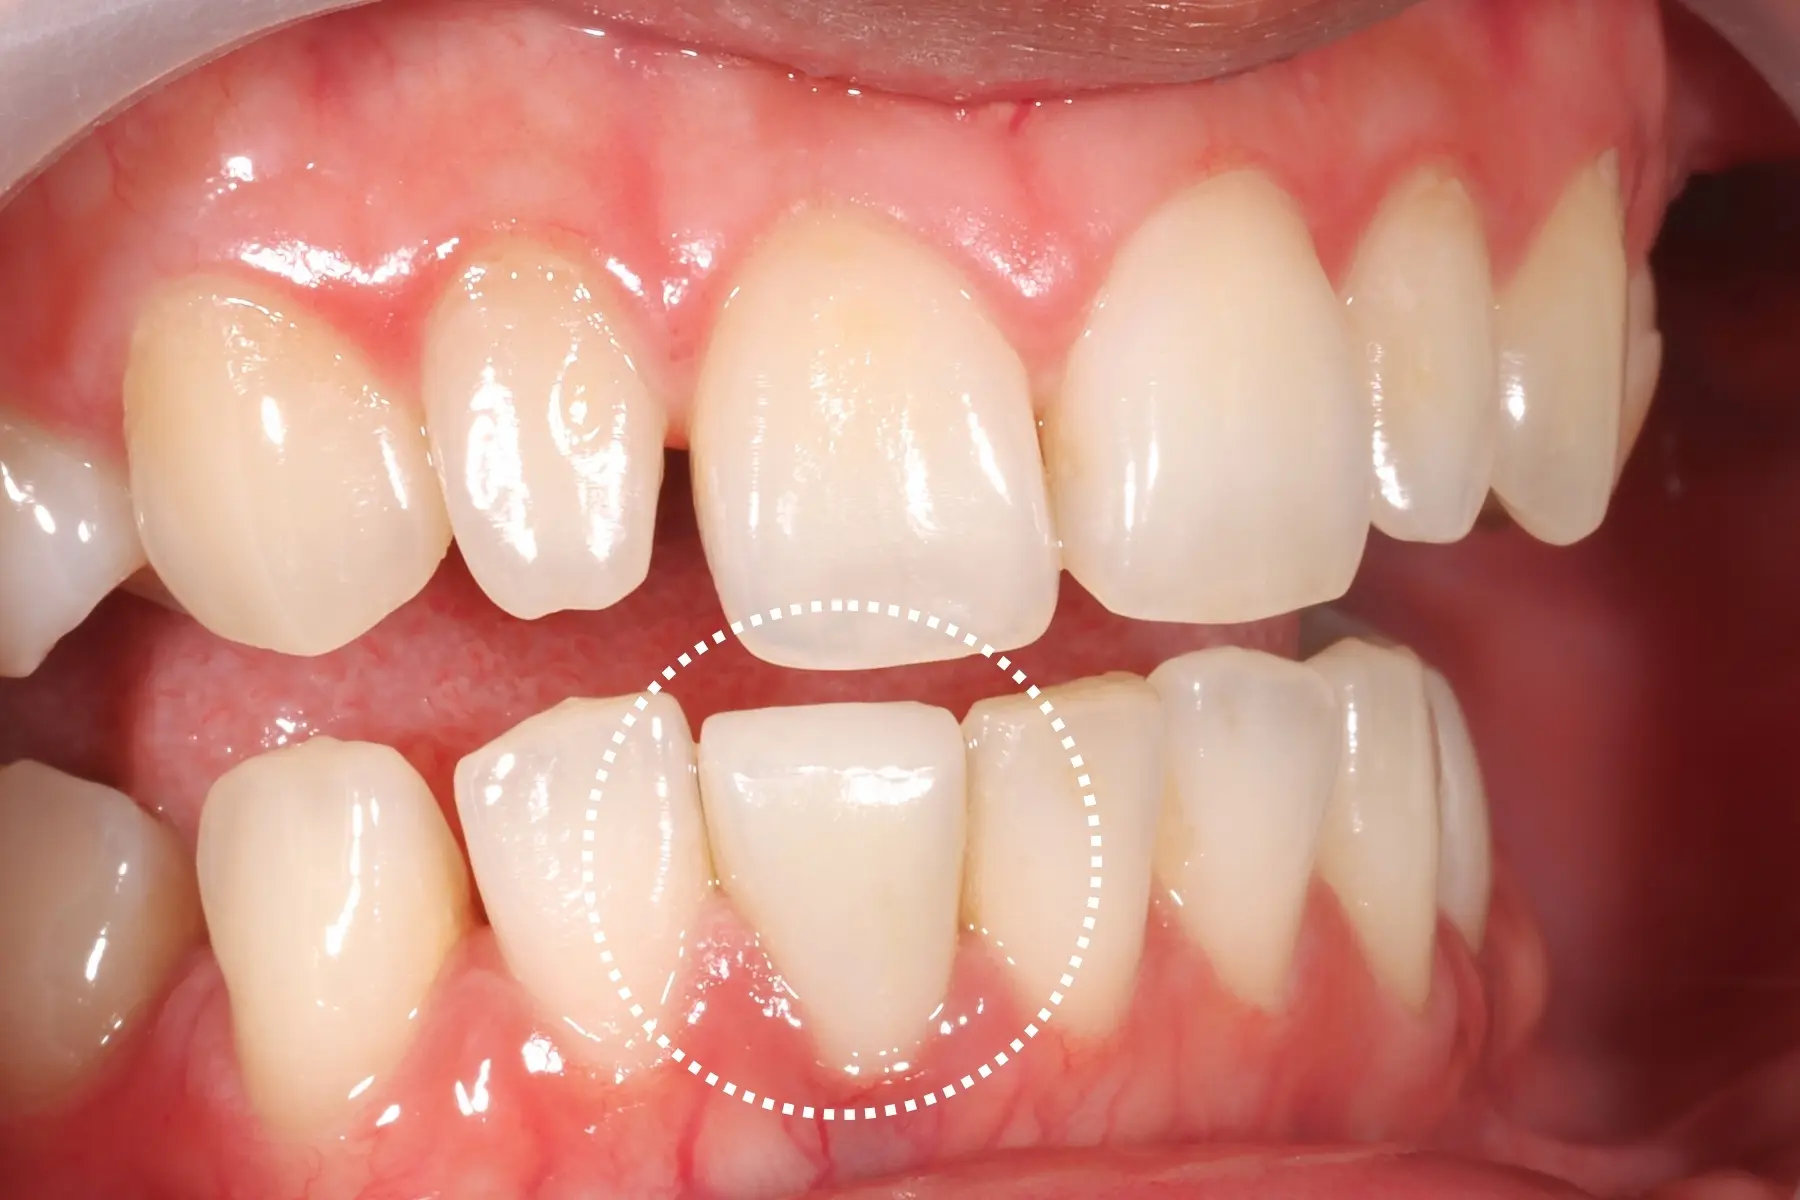

矯正完成下排前牙出現黑三角

• 術前 44

術後 42

仿生美學樹脂

主治醫師

• 陳暐文

治療時間

單次療程

主訴

門牙有縫、牙齒形狀偏方,笑起來不夠自然